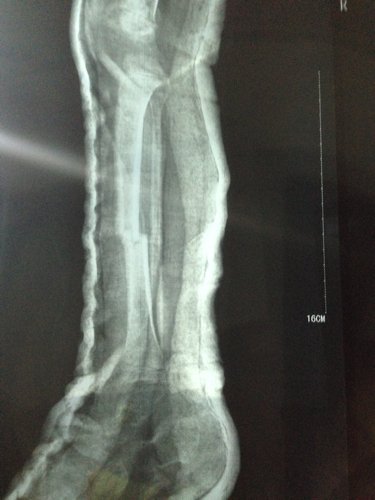

男孩三周岁 5-9 被电动车撞,右小腿胫骨骨折,正位对线良好,侧位错位三分之一。现差不多六周,前两天腿甩痛了就近急诊拍片,医生说骨头在长的,一周后把石膏拆掉吧,否则肌肉萎缩影响走路的,请各位医生指点一下,错位情况下,石膏拆了会影响恢复吗?因为两段骨头没合上阿,我上传一张之前的片子,请大家帮忙看一下。